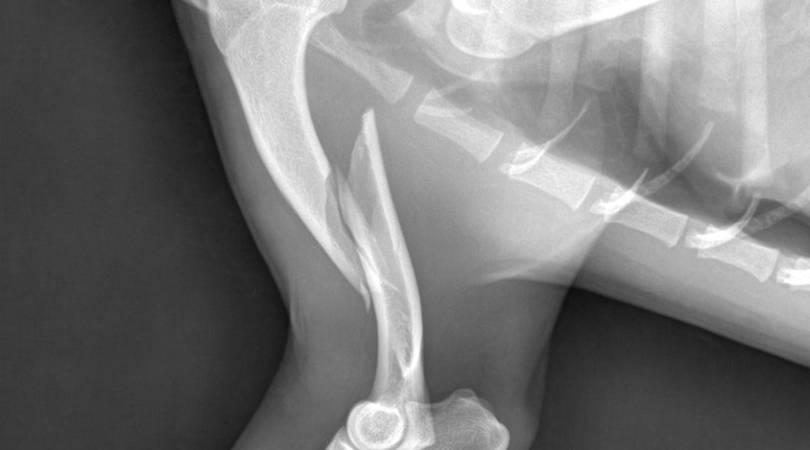

La vecina Natalia Olivera se comunicó con Chacabuco en Red solicitando difusión de una rifa que tiene como fin financiar la operación de su mascota, quien fue atropellada y sufrió una fractura.

Cualquiera que quiera colaborar con la adquisición de un numerito, comunicarse al 2352442509. La cirugía tiene un costo de 670 mil pesos.